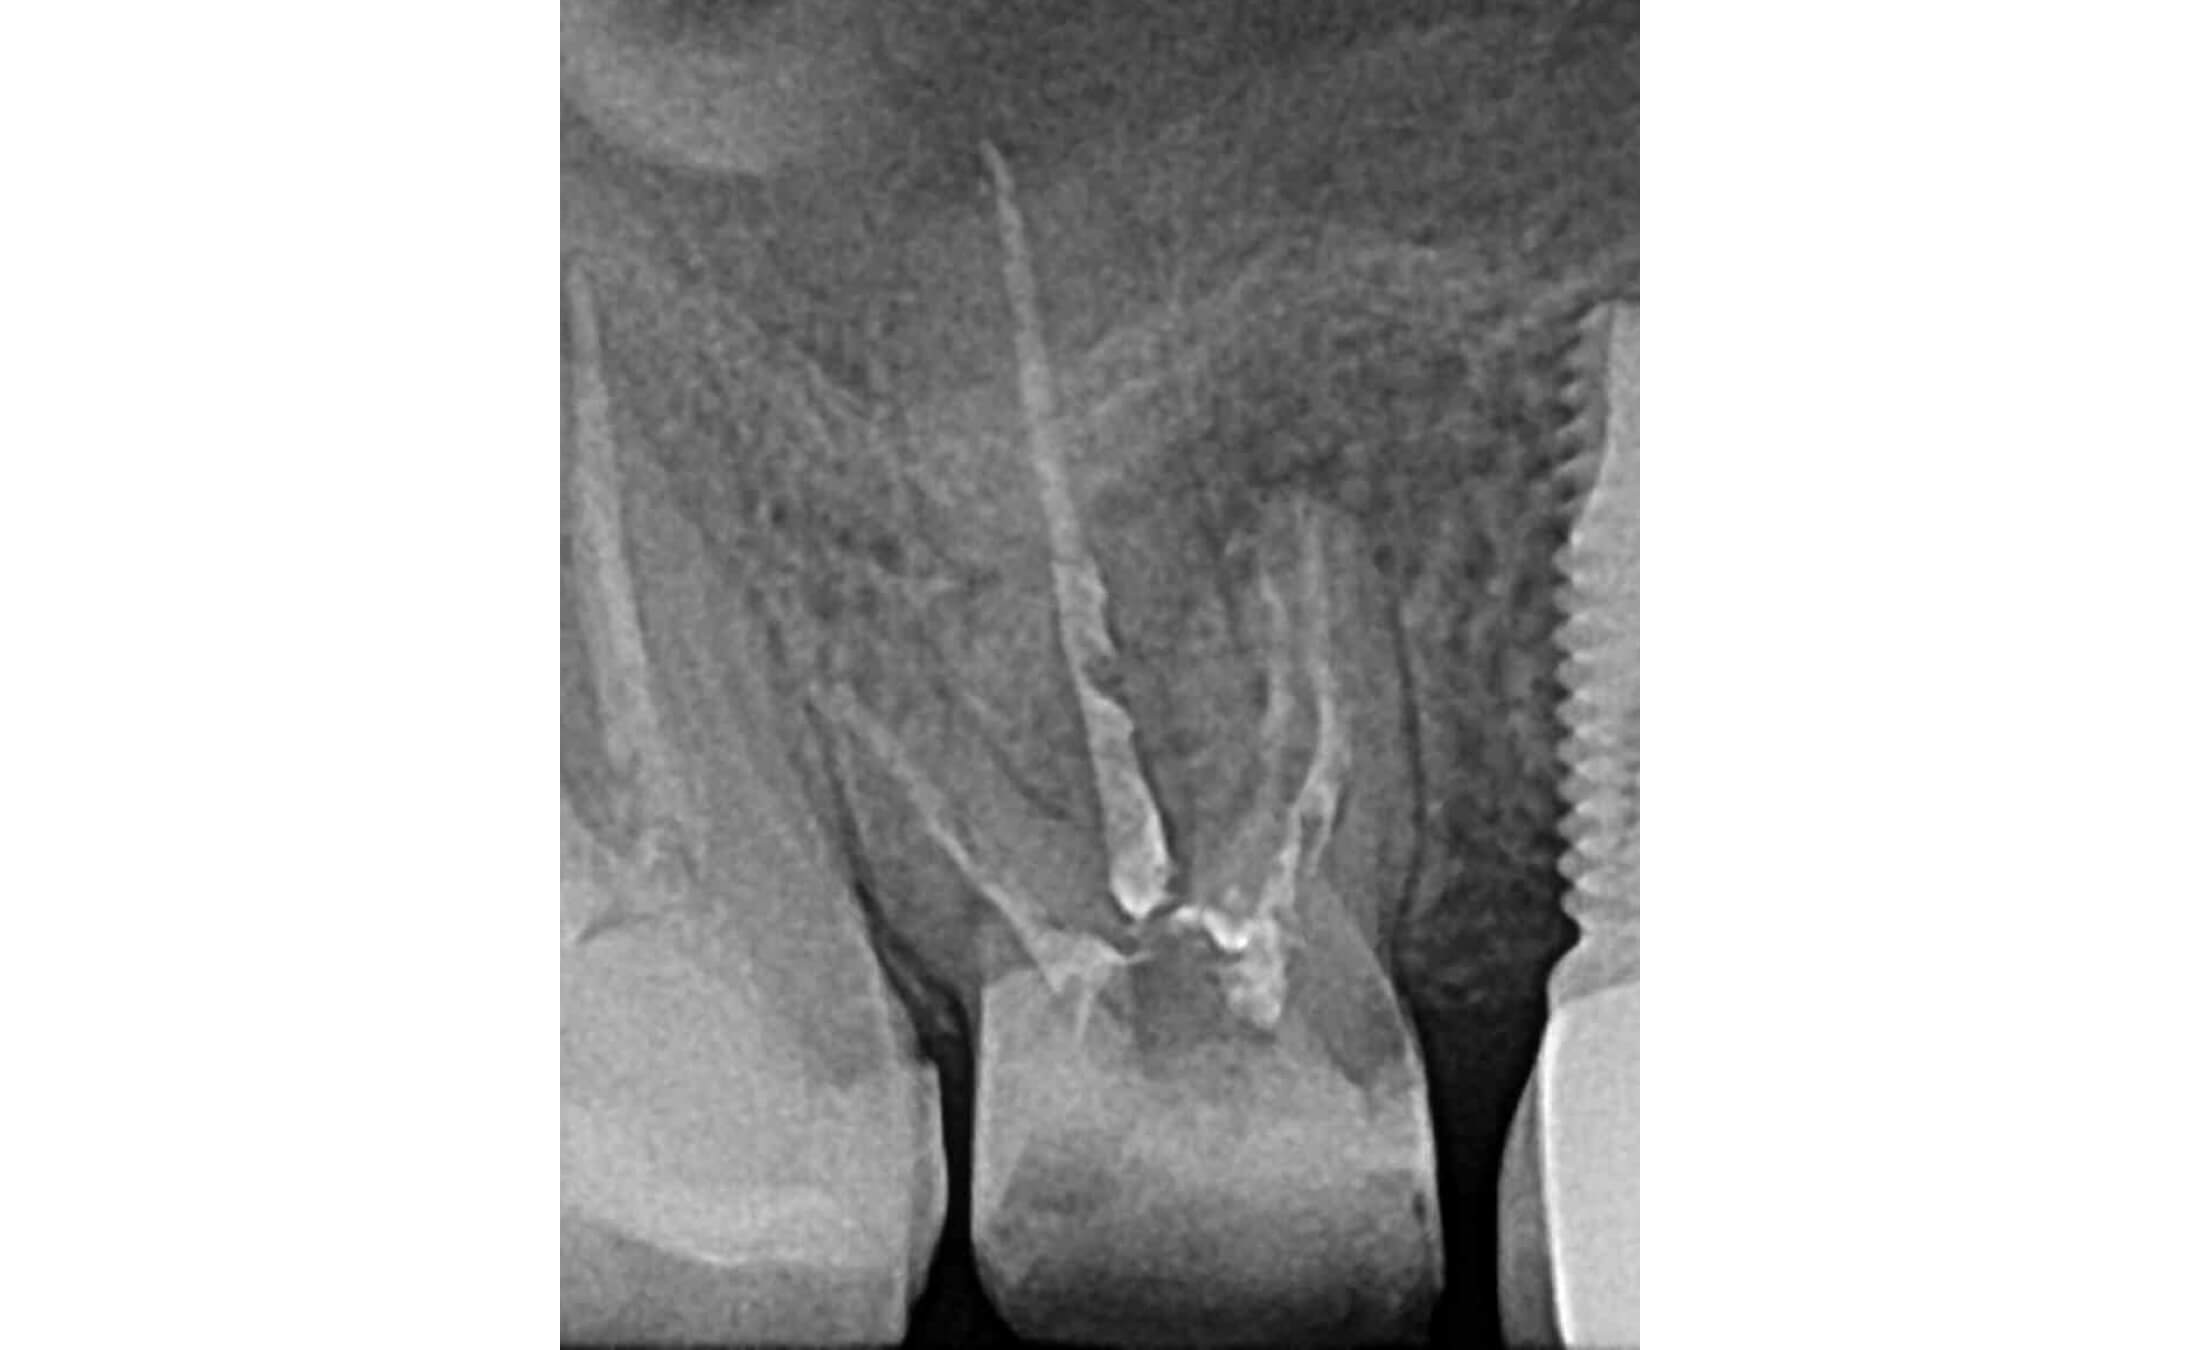

1. A case of tooth #16 presenting with chronic apical periodontitis featuring extensive mesiobuccal root periapical pathology (4-5mm lesion) and draining sinus tract, with evidence of prior incomplete endodontic treatment. (Image 1-4)

2. During the initial appointment, the following treatment was performed: complete revision of the root canal system, removal of existing obturation material, and thorough mechanical instrumentation combined with chemical disinfection. The canals were then temporarily obturated with a calcium hydroxide-based medication for a period of two weeks. (Image 5)